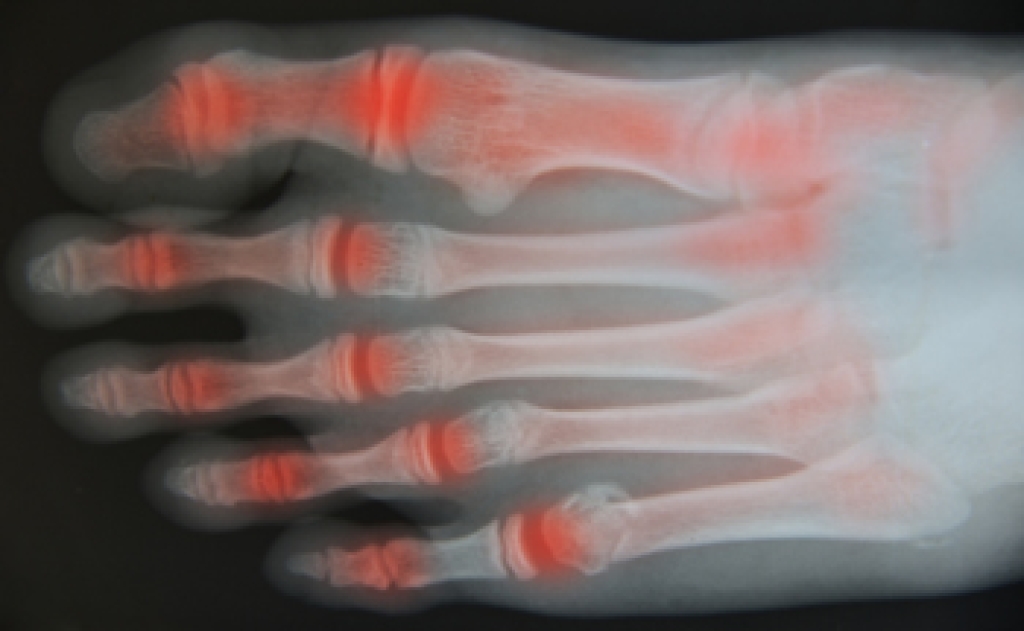

Peripheral neuropathy occurs when nerves outside the brain and spinal cord are damaged, disrupting communication with the feet. Many patients first notice numbness, tingling, burning, or sharp shooting pain that often begins in the toes and gradually spreads upward. Reduced sensation can make it difficult to feel temperature, pressure, or injury, increasing the risk of unnoticed blisters, sores, and balance problems while walking. Diabetes is the most common cause, as long-term elevated blood sugar damages nerve fibers and circulation. Other causes include traumatic injury, poor blood flow, infections, autoimmune disorders, vitamin deficiencies, kidney or liver disease, toxin exposure, and certain cancers. A podiatrist can perform neurological and vascular testing, evaluate skin integrity, manage pressure areas, and provide medical care to help prevent infection and tissue breakdown. If you have foot problems associated with peripheral neuropathy, it is suggested that you make an appointment with a podiatrist for an exam, diagnosis, and ongoing treatment.

Neuropathy is a condition that leads to damage to the nerves in the body. Peripheral neuropathy, or neuropathy that affects your peripheral nervous system, usually occurs in the feet. Neuropathy can be triggered by a number of different causes. Such causes include diabetes, infections, cancers, disorders, and toxic substances.